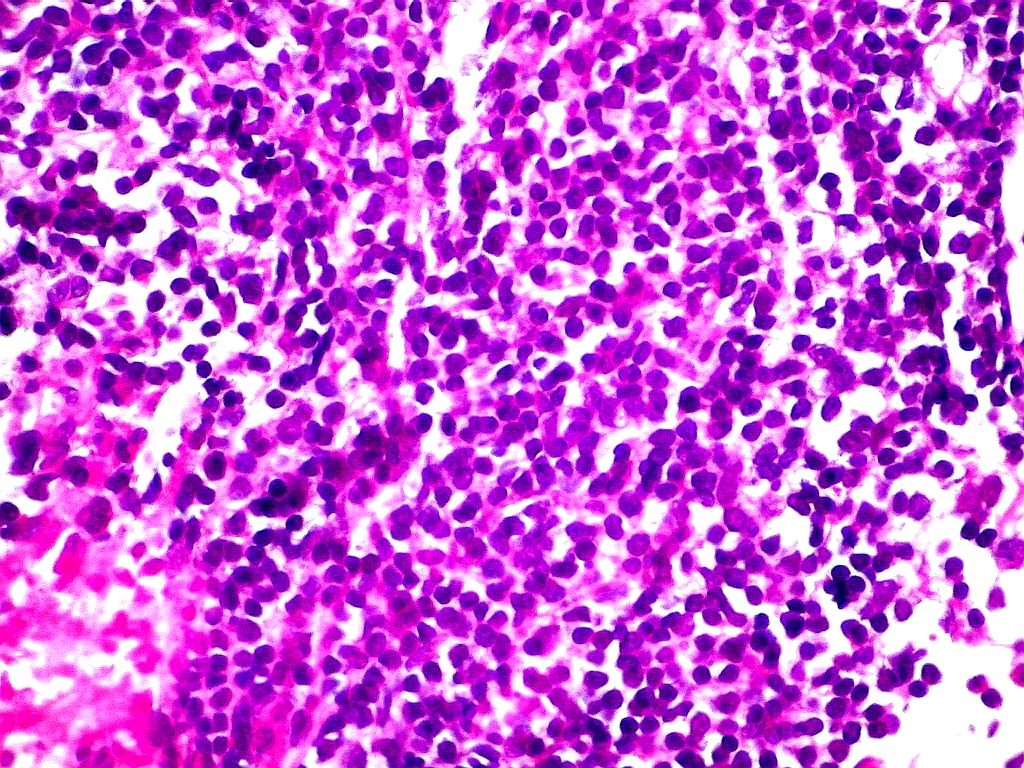

INI1.

Antígeno nuclear presente em todas as células normais.

Sua ausência é importante marcador do tumor teratóide

rabdóide atípico (metade direita do campo). Na metade

esquerda, vaso com células positivas. Os vasos não

pertencem ao tumor, mas o invadem a partir dos tecidos infiltrados. |